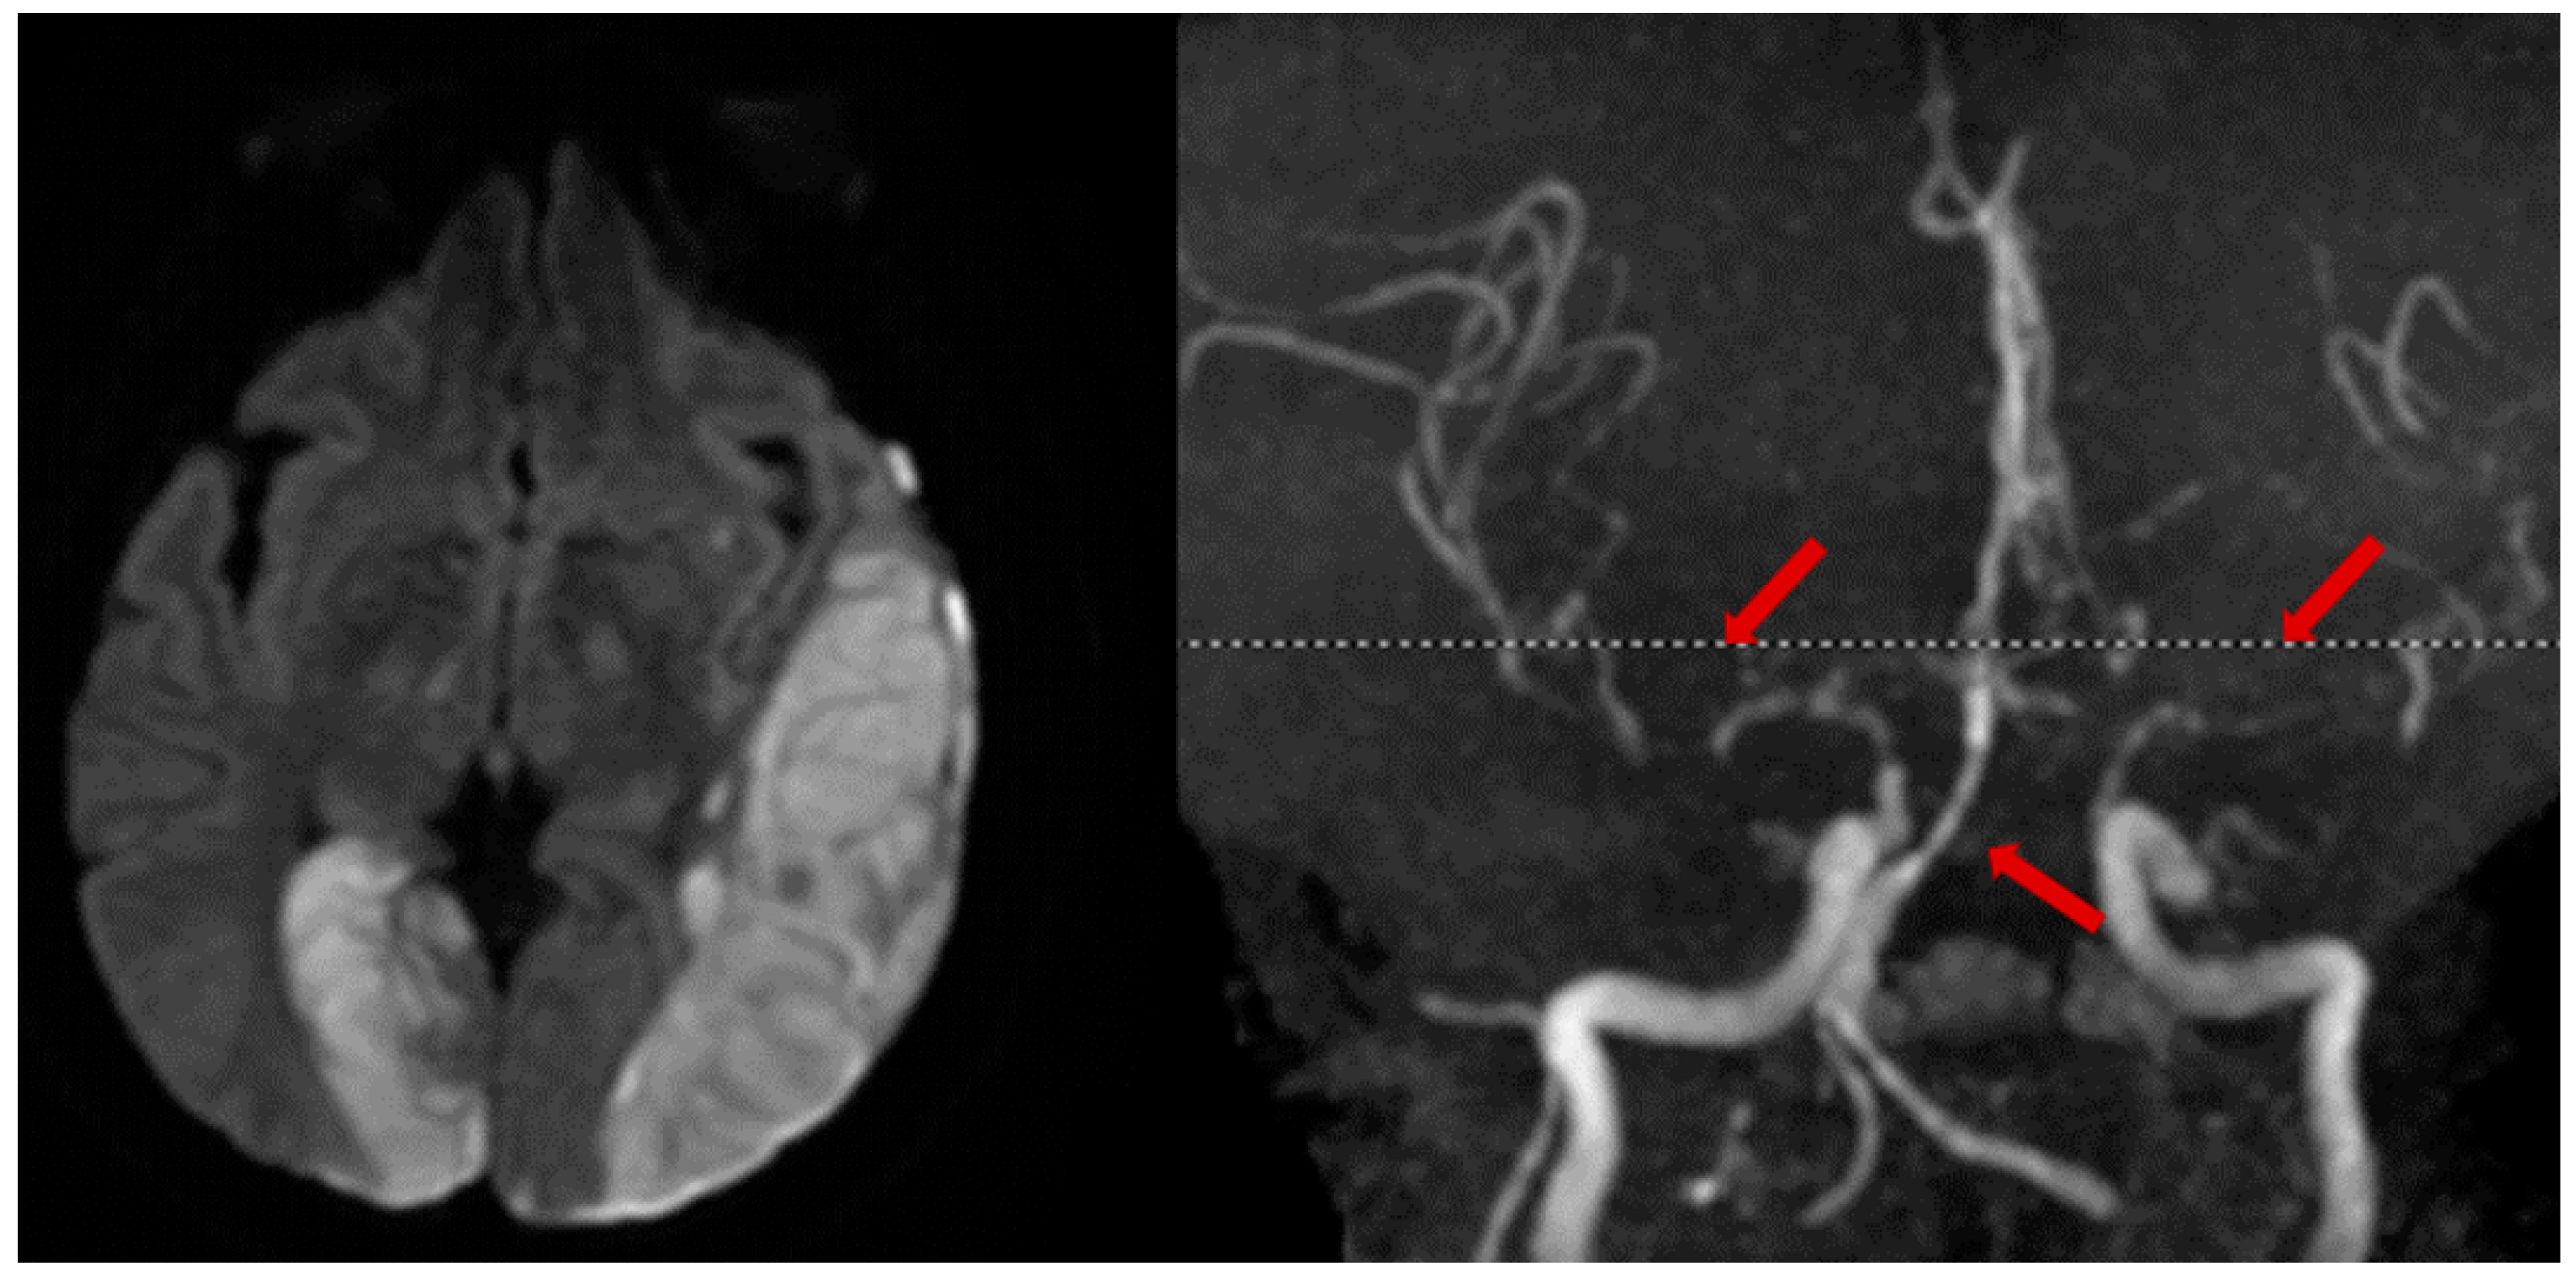

2.3. Cervical Artery Dissection

3.3.1. Angiography

3.3.2. MR Vessel Wall Imaging: An Emerging Diagnostic Tool